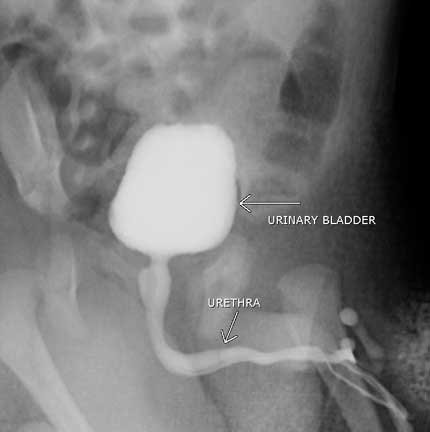

Cistouretrografía de vaciado. Vista oblicua de un varón joven durante el vaciado.

Nota: Las imágenes se muestra para fines ilustrativos. No trate de sacar conclusiones comparando esta imagen con otras en el sitio. Solamente los radiólogos calificados deben interpretar las imágenes.